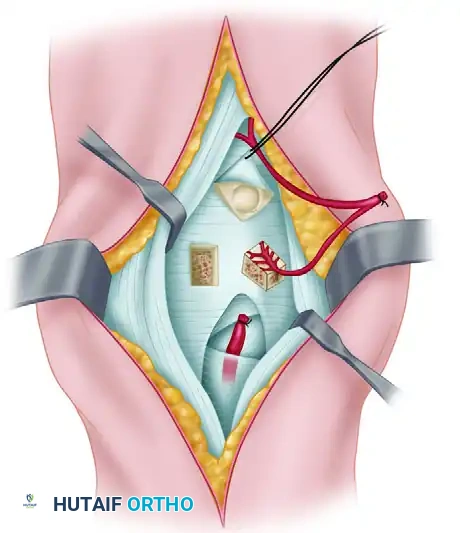

The Volar (Henry) Approach to the Wrist

Indications: ORIF of volar distal radius fractures, scaphoid waist fractures, perilunate dislocations, and volar marginal lip fractures.

Positioning: Supine, arm on a hand table, forearm supinated.

Step-by-Step Surgical Technique:

1. Incision: A longitudinal incision is made over the course of the Flexor Carpi Radialis (FCR) tendon, zig-zagging across the wrist crease if extending into the palm.

2. Superficial Dissection: Incise the superficial fascia. Identify and protect the palmar cutaneous branch of the median nerve, which lies ulnar to the FCR tendon.

3. Internervous Plane: Incise the FCR tendon sheath and retract the FCR tendon ulnarly (protecting the median nerve). Retract the radial artery radially.

4. Deep Dissection: Expose the deep fascial layer covering the Flexor Pollicis Longus (FPL) and the pronator quadratus (PQ).

5. Pronator Quadratus Elevation: Incise the PQ along its radial and distal borders (the "L" incision) and elevate it ulnarly to expose the volar surface of the distal radius.

6. Capsulotomy: If accessing the carpus (e.g., for scaphoid ORIF), perform a longitudinal or T-shaped volar capsulotomy, taking care to repair the strong volar extrinsic ligaments (RSC, LRL) upon closure.

Closure: The volar capsule is repaired if opened. The pronator quadratus is reapproximated to the radial border to cover the hardware and prevent flexor tendon irritation. The FCR sheath is left open to prevent stenosis.